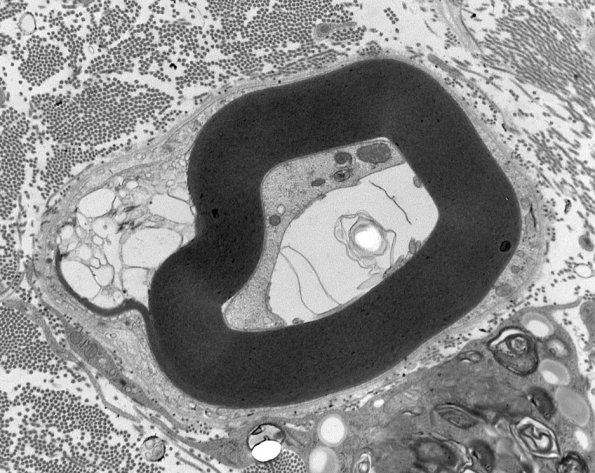

4F1  GBS, fulminant (Case 4) 136a - Copy

4F1,2 In this case there appears to be equivocal demyelination. (electron micrographs)